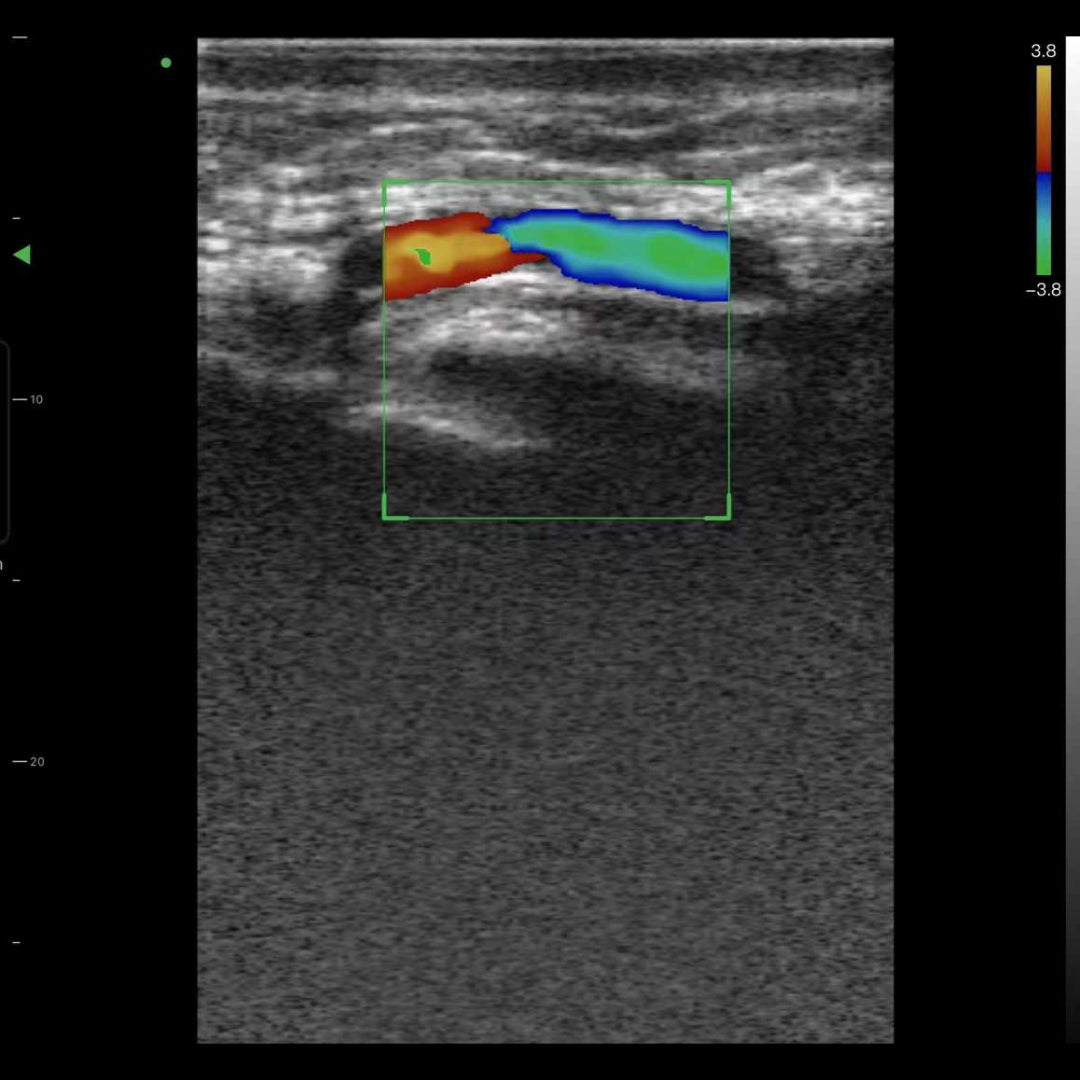

• Visualización de vasos para cirugía facial reconstructiva/cosmética.

Imágenes de la vida real

Nuestros dispositivos reproducen una excelente calidad de imagen.